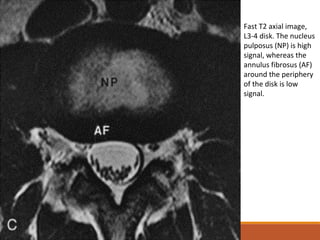

Fast T2 axial image,

L3-4 disk. The nucleus

pulposus (NP) is high

signal, whereas the

annulus fibrosus (AF)

around the periphery

of the disk is low

signal.

◦Na RM, o disco ideal normal possui sinal de baixa intensidade em

T1, tendo sinal discretamente mais baixo que a medula vermelha

adjacente normal e muito similar ao músculo.

◦As imagens em T2 mostram sinal difuso de intensidade alta em

todo o disco, exceto pelas fibras externas do anel, que possuem

sinal homogeneamente baixo.